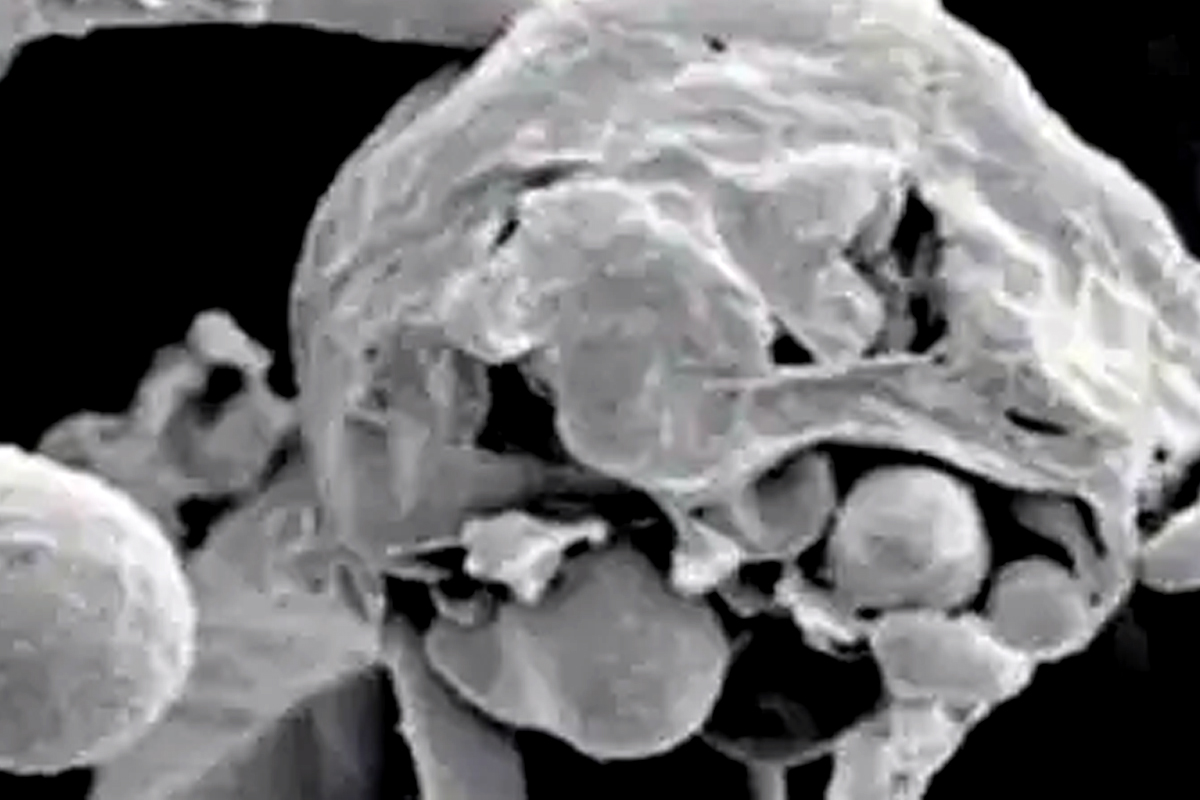

पाटणा, 20 मे : कोरोनाच्या संकटाशी दोन हात करत असतानाच काही दिवसांपूर्वी ब्लॅक फंगस (Black Fungus) या आजारानं डोकं वर काढलं आहे. या आजाराचे रुग्ण आता समोर येऊ लागले असतानाच आता आणखी एक व्हाईट फंगस (White fungus) नावाचा अधिक धोकादायक आजार समोर आला आहे. हा ब्लॅक फंगसपेक्षा अधिक धोकादायक (Dangerous) असून यामुळंही फुफ्फुसांमध्ये संसर्ग होत असल्याचं पाहायला मिळालं आहे. तसंच यामुळं त्वचा, नखं, तोंडाच्या आतील भाग, आतडे, किडणी प्रायव्हेट पार्ट आणि मेंदू अशा सर्वच अवयवांवर परिणाम होत असल्याचं समोर आलं आहे. पाटण्याच्या या सर्व रुग्णांमध्ये कोरोनाची लक्षणं होती. त्यांच्या सर्व चाचण्या झाल्या. पण कोणत्याही चाचणीत ते कोरोना पॉझिटिव्ह आढळले नाही. कोरोनाच्या औषधांचाही त्यांच्यावर परिणा होत नव्हता. त्यानंतर अधिक तपासण्या करण्यात आल्यानंतर हा व्हाईट फंगसचा प्रकार असल्याचं समोर आलं. त्यानंतर अँटि फंगल औषधानं हे रुग्ण बरे झाले. या आजाराचं निदान कठीण आहे. पण अनेक रिपोर्ट याच निगेटिव्ह येतात. पण कोरोनासारखी लक्षणं आणि कफमुळं निघणाऱ्या द्रवाच्या तपासणीतून याचं निदान होतं. VIDEO: कोरोना काळात लग्नासाठी जमली गर्दी; पोलिसांनी बेडूक उड्यांची शिक्षा देत काढली वरात हा आजार गंभीर आणि धोकादायक असला तरी यापासून बचाव करणं अत्यंत सोपं असल्याचं तज्ज्ञांचं मत आहे. एखाद्या रुग्णाला ऑक्सिजन दिला जात असेल तर त्याच्या उपकरणामध्ये कोणताही बॅक्टेरिया असता कामा नये. ऑक्सिजन सिलिंडरमध्ये ह्युमिडिफायरसाठी स्टर्लाईज वॉटरचा वापर करायला हवा. त्यामुळं फंगसपासून संरक्षण करण्यासाठी ऑक्सिजन घेणाऱ्याला विषाणूची लागण झालेली नसावी. ब्लॅक फंगस म्हणजे म्युकरमायकोसिसची भीती वाढत असतानाच आता बिहारमध्ये ब्लॅक फंगचेही 4 रुग्ण आढळल्यानं धोका वाढच चालला आहे. हा आजार होण्याचं कारणही रोग प्रतिकारशक्तीची कमतरता असल्याचं डॉक्टरांनी म्हटलं आहे. तसंच मधुमेह आणि अँटिबायोटिक किंवा स्टेरॉईड दीर्घकाळ घेणाऱ्यांनाही याचा धोका आहे. कॅन्सरच्या रुग्णांनाही या फंगसपासून धोका आहे. नवजात बाळांमध्ये हा आजार डायपर कँडिडोसिस म्हणून समोर येतो.